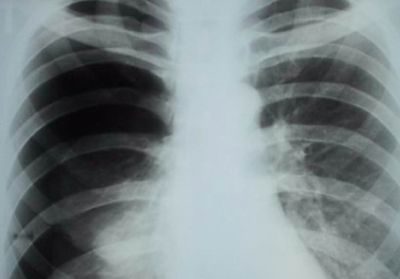

- рентгенография органов грудной клетки;

- рентгенографию;

- рентгенографии грудной клетки;